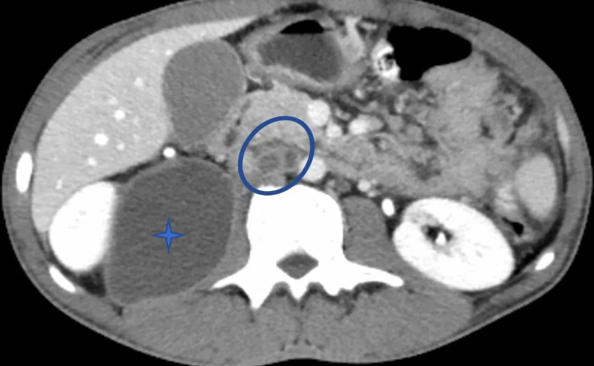

沙希德慕名来到上海瑞金医院,常规检查提示他营养状况很差,并且贫血。消化内科钟捷主任医师团队仔细询问了病史,完善了胰腺影像学检查,检查发现胰腺形态饱满,胰头后方、肠系膜多发周边环形强化灶,部分伴有钙化,并且右侧腰大肌旁也可见一个较大的周边环形强化灶,回盲部及盆腔内回肠连续性肠壁增厚,肠系膜肿胀。

“影像学上因出现肝门、胰头周围这些少见部位的多发淋巴结周边环形强化,肠系膜亦可见该征象,部分伴钙化,且主要分布在回结肠血管分布区,回盲部及盆腔回肠连续性肠壁增厚,这是结核感染的影像学征象。”赵雪松医生说,加之考虑患者来自卫生条件较差的地区,肠结核合并淋巴结结核、腹膜结核、右侧腰大肌冷脓肿的可能性很大。